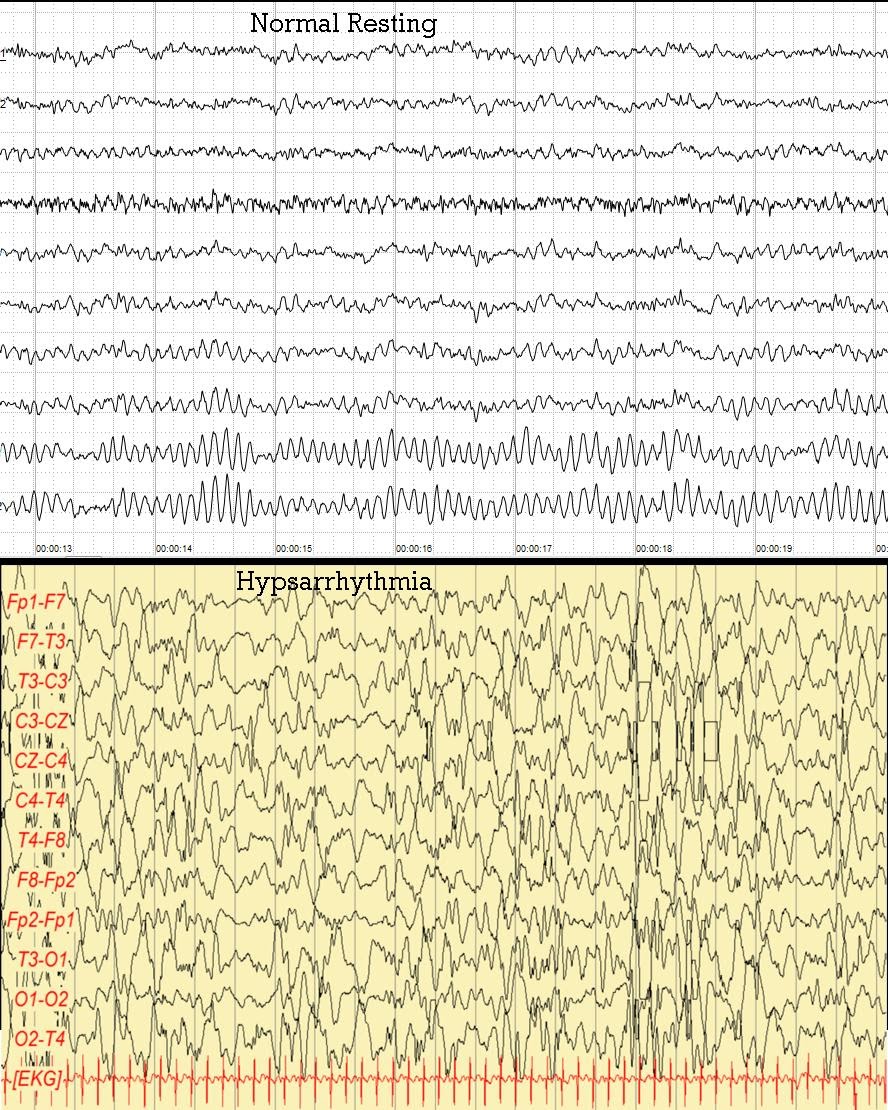

Αρχικά, το εγκεφαλογράφημα είναι μια ανώδυνη διαγνωστική εξέταση και χρησιμοποιείται για την διάγνωση εγκεφαλικών παθήσεων και βλαβών. Το παθολογικό εγκεφαλογράφημα, ενός παιδιού με σύνδρομο West θα έχει διάχυτες, βαθιές, παροξυσμικές ανωμαλίες και ο τύπος αυτός ονομάζεται υψαρρυθμία (hypsarrythmia).

Εικόνα 2.: Φυσιολογικό εγκεφαλογράφημα – Εγκεφαλογράφημα με υψαρρυθμία